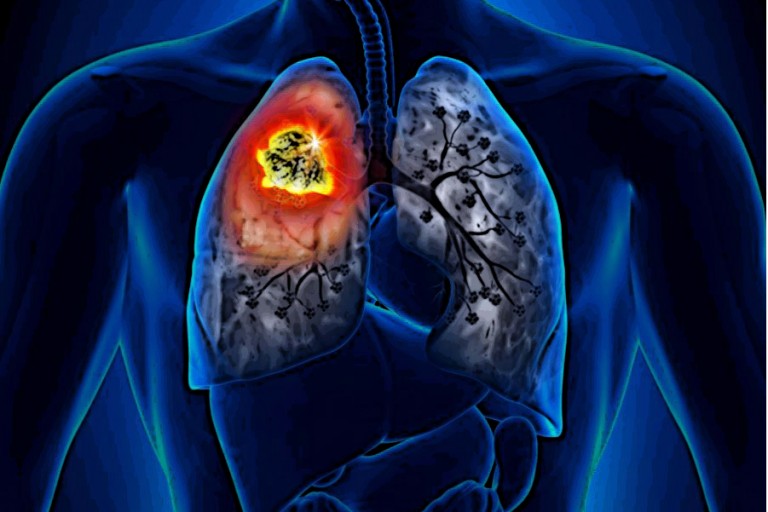

오늘은 많은 분들이 궁금해하는 폐암 초기 증상에 대해 이야기하려 합니다. 폐암은 한국인의 사망 원인 1위인 암으로, 초기에는 뚜렷한 증상이 없거나 감기와 비슷해 간과하기 쉽습니다.

폐암 초기증상 하지만 몸이 보내는 작은 신호들을 놓치지 않고 조기에 발견하여 치료를 시작하는 것이 매우 중요합니다. 지금부터 폐암의 10가지 주요 초기 증상들을 꼼꼼히 살펴보고, 건강을 위한 첫걸음을 함께 시작해 볼까요? 💨

폐암은 암세포가 커지거나 주변 기관으로 전이되면서 다양한 증상을 유발합니다. 증상이 나타났을 때는 이미 어느 정도 진행된 경우가 많으므로, 아래 증상들을 주의 깊게 살펴봐야 합니다. 다음은 폐암 환자들이 흔히 겪는 10가지 주요 초기 증상입니다.